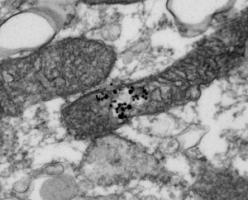

PARKINSON : Cibler les mitochondries pour booster les neurones

Actualité publiée le 21/02/2017PARKINSON : Rétablir les lipides des mitochondries pour bloquer la maladie

LUPUS : La nouvelle option thérapeutique qui déstresse les mitochondries